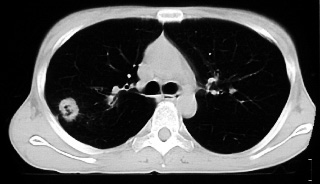

- 胸部CTにて、右上肺野に、spiculaを伴った腫瘤を2ヶ所認め、肺癌が疑われる。

- 両膝、手指関節痛およびばち状指を主訴に来院。胸部CTにて肺癌が疑われ、骨転移検索目的の骨シンチにて、両手足に集積亢進を認めた。右上葉切除術施行(double

primaryの腺癌)直後より関節の症状は消失し、5ヶ月後の骨シンチも正常化した。以上より、肺癌に伴う肥大性骨関節症と確認されたが、骨シンチでの異常集積は手足のみで、特徴的とされる長管骨への集積増強がなかったという点で、非典型的である。